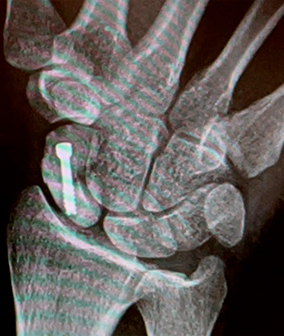

Fotos quirúrgicas